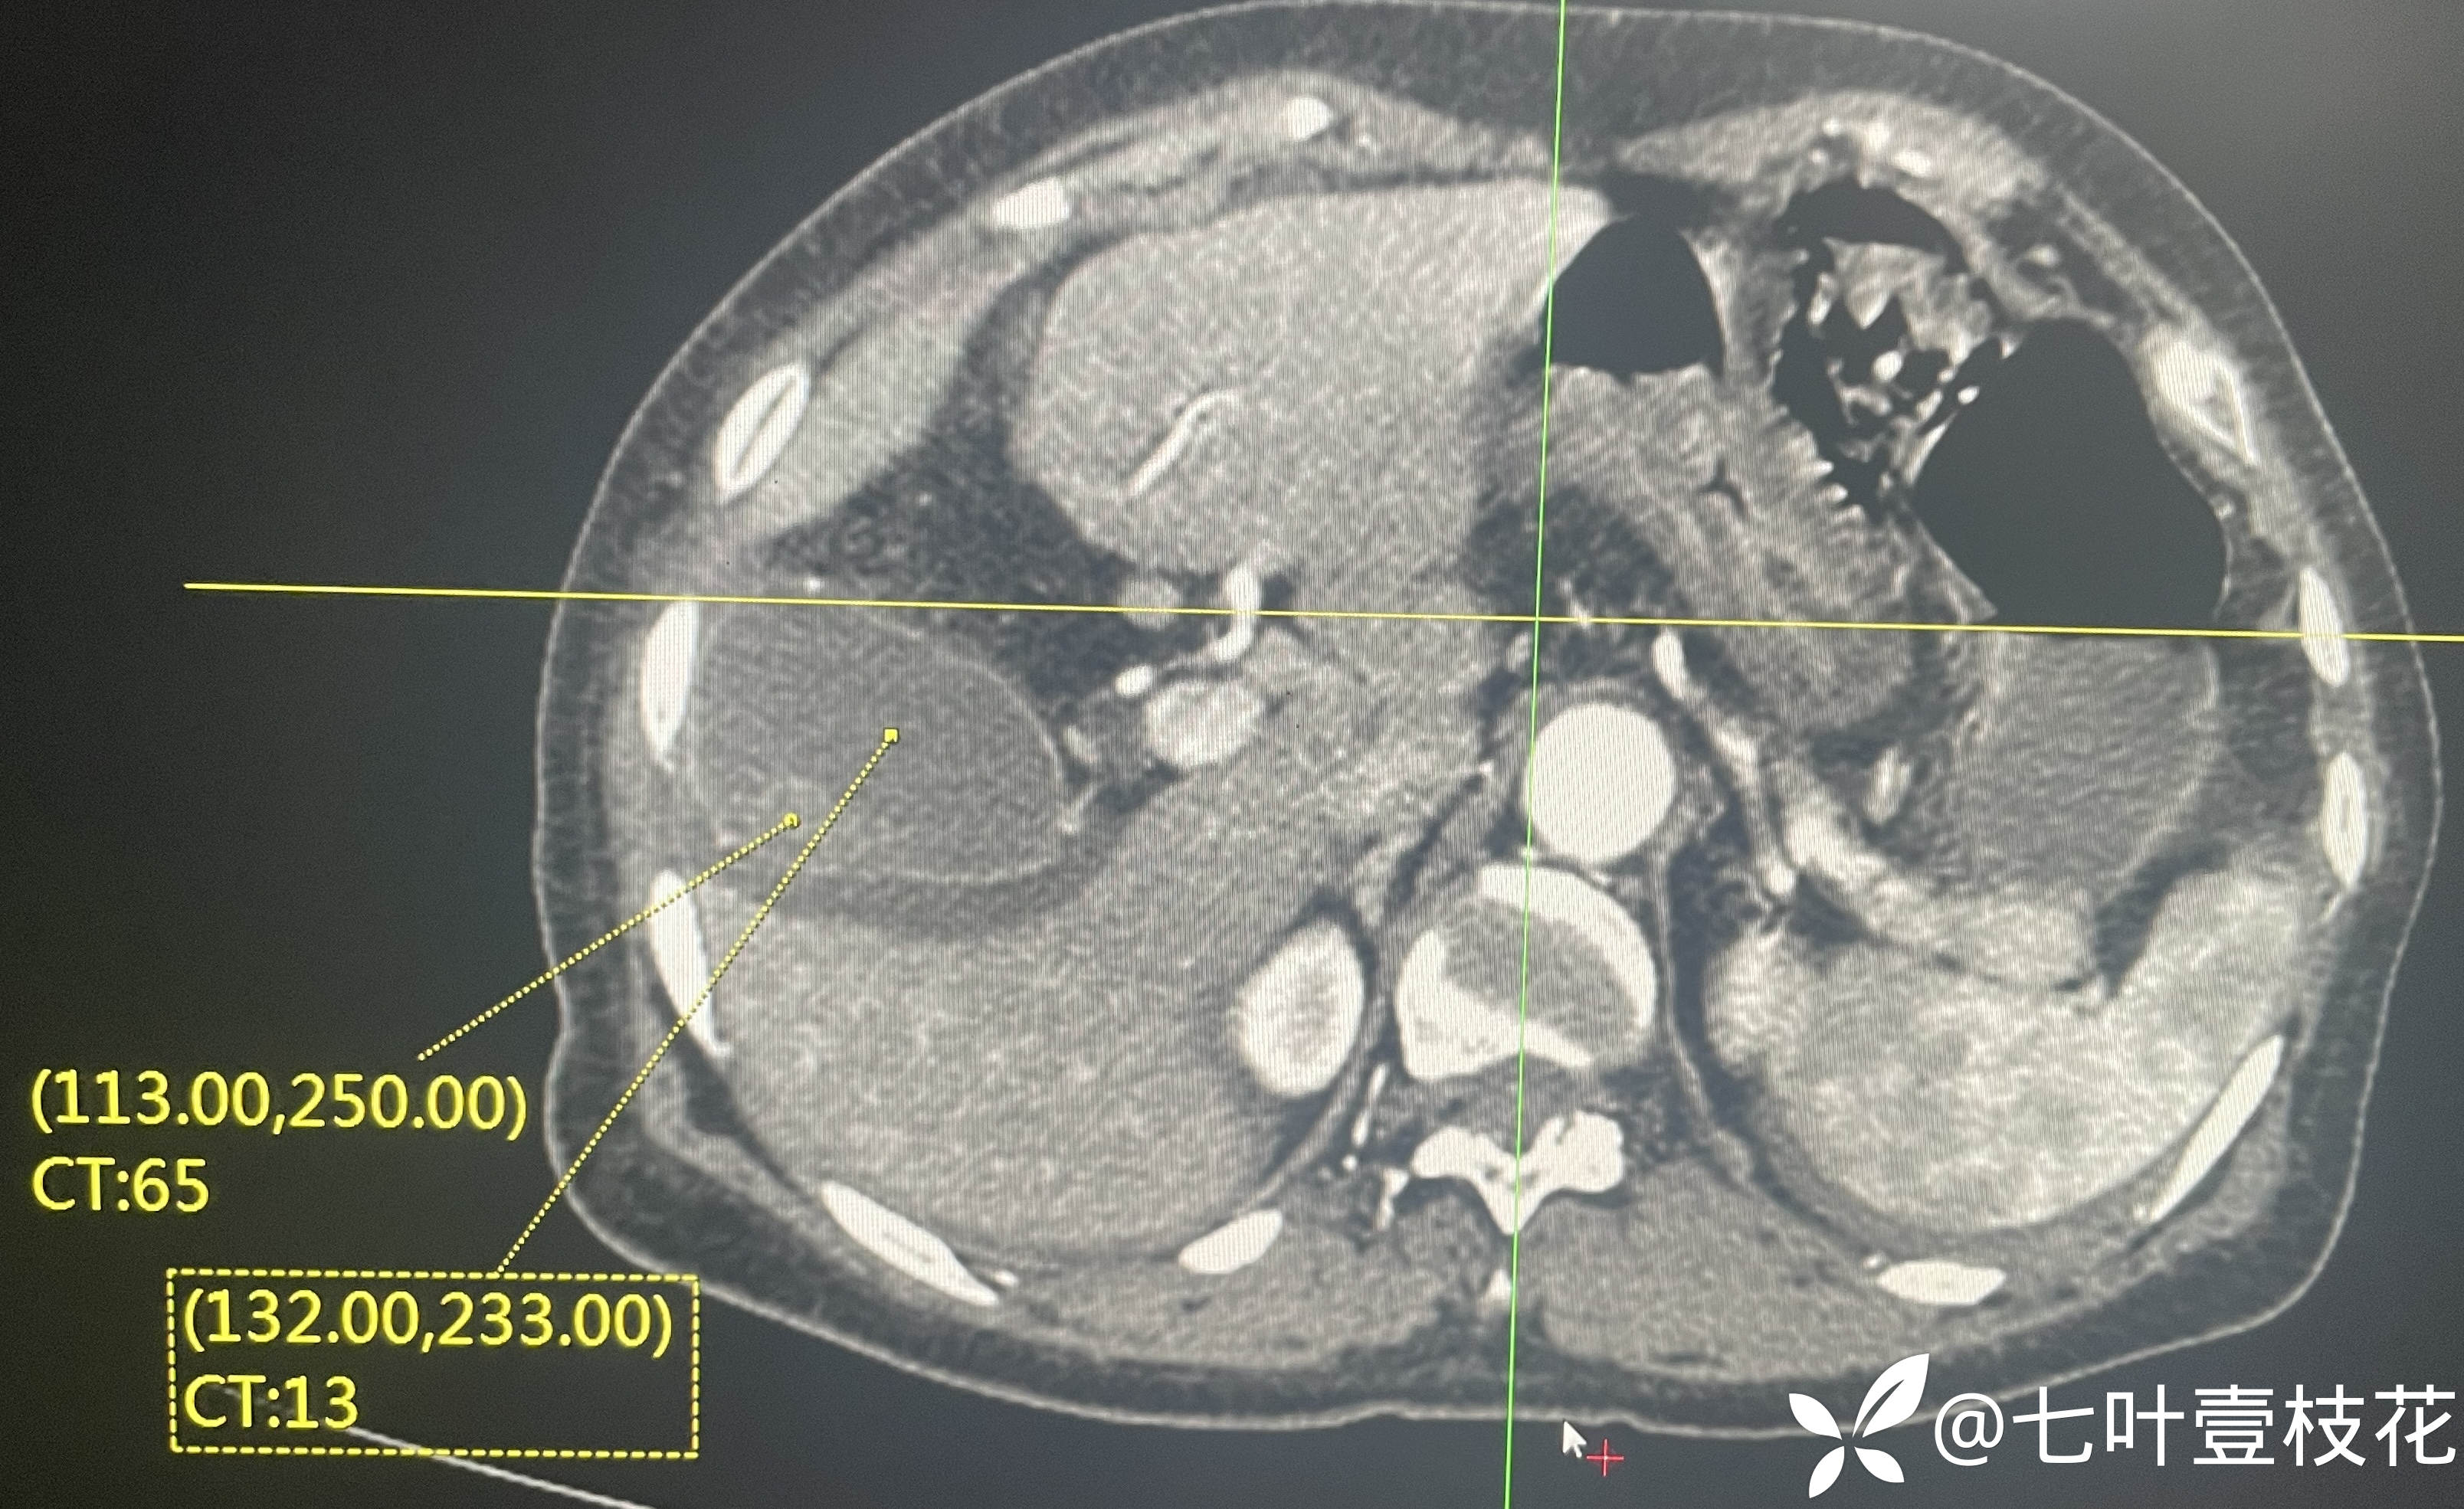

8月5日,入院第一天全腹CT

下面是腹主动脉CTA动态视频(动脉期和静脉期)及文字报告:

8月7日,入院第三天腹主动脉CTA

这位患者是8月5日凌晨入院的,第二天完善了肠镜,经治疗后到8月6日未再便血,腹痛也有所缓解,8月7日出现解黄色稀水样便3次,每次约100-200ml,其内可见少许类似肠道组织样絮状物,腹痛加剧,后来完善腹主动脉CTA后转上级医院进一步治疗了。病检目前未回,上级医院检查结果后续随访补充。